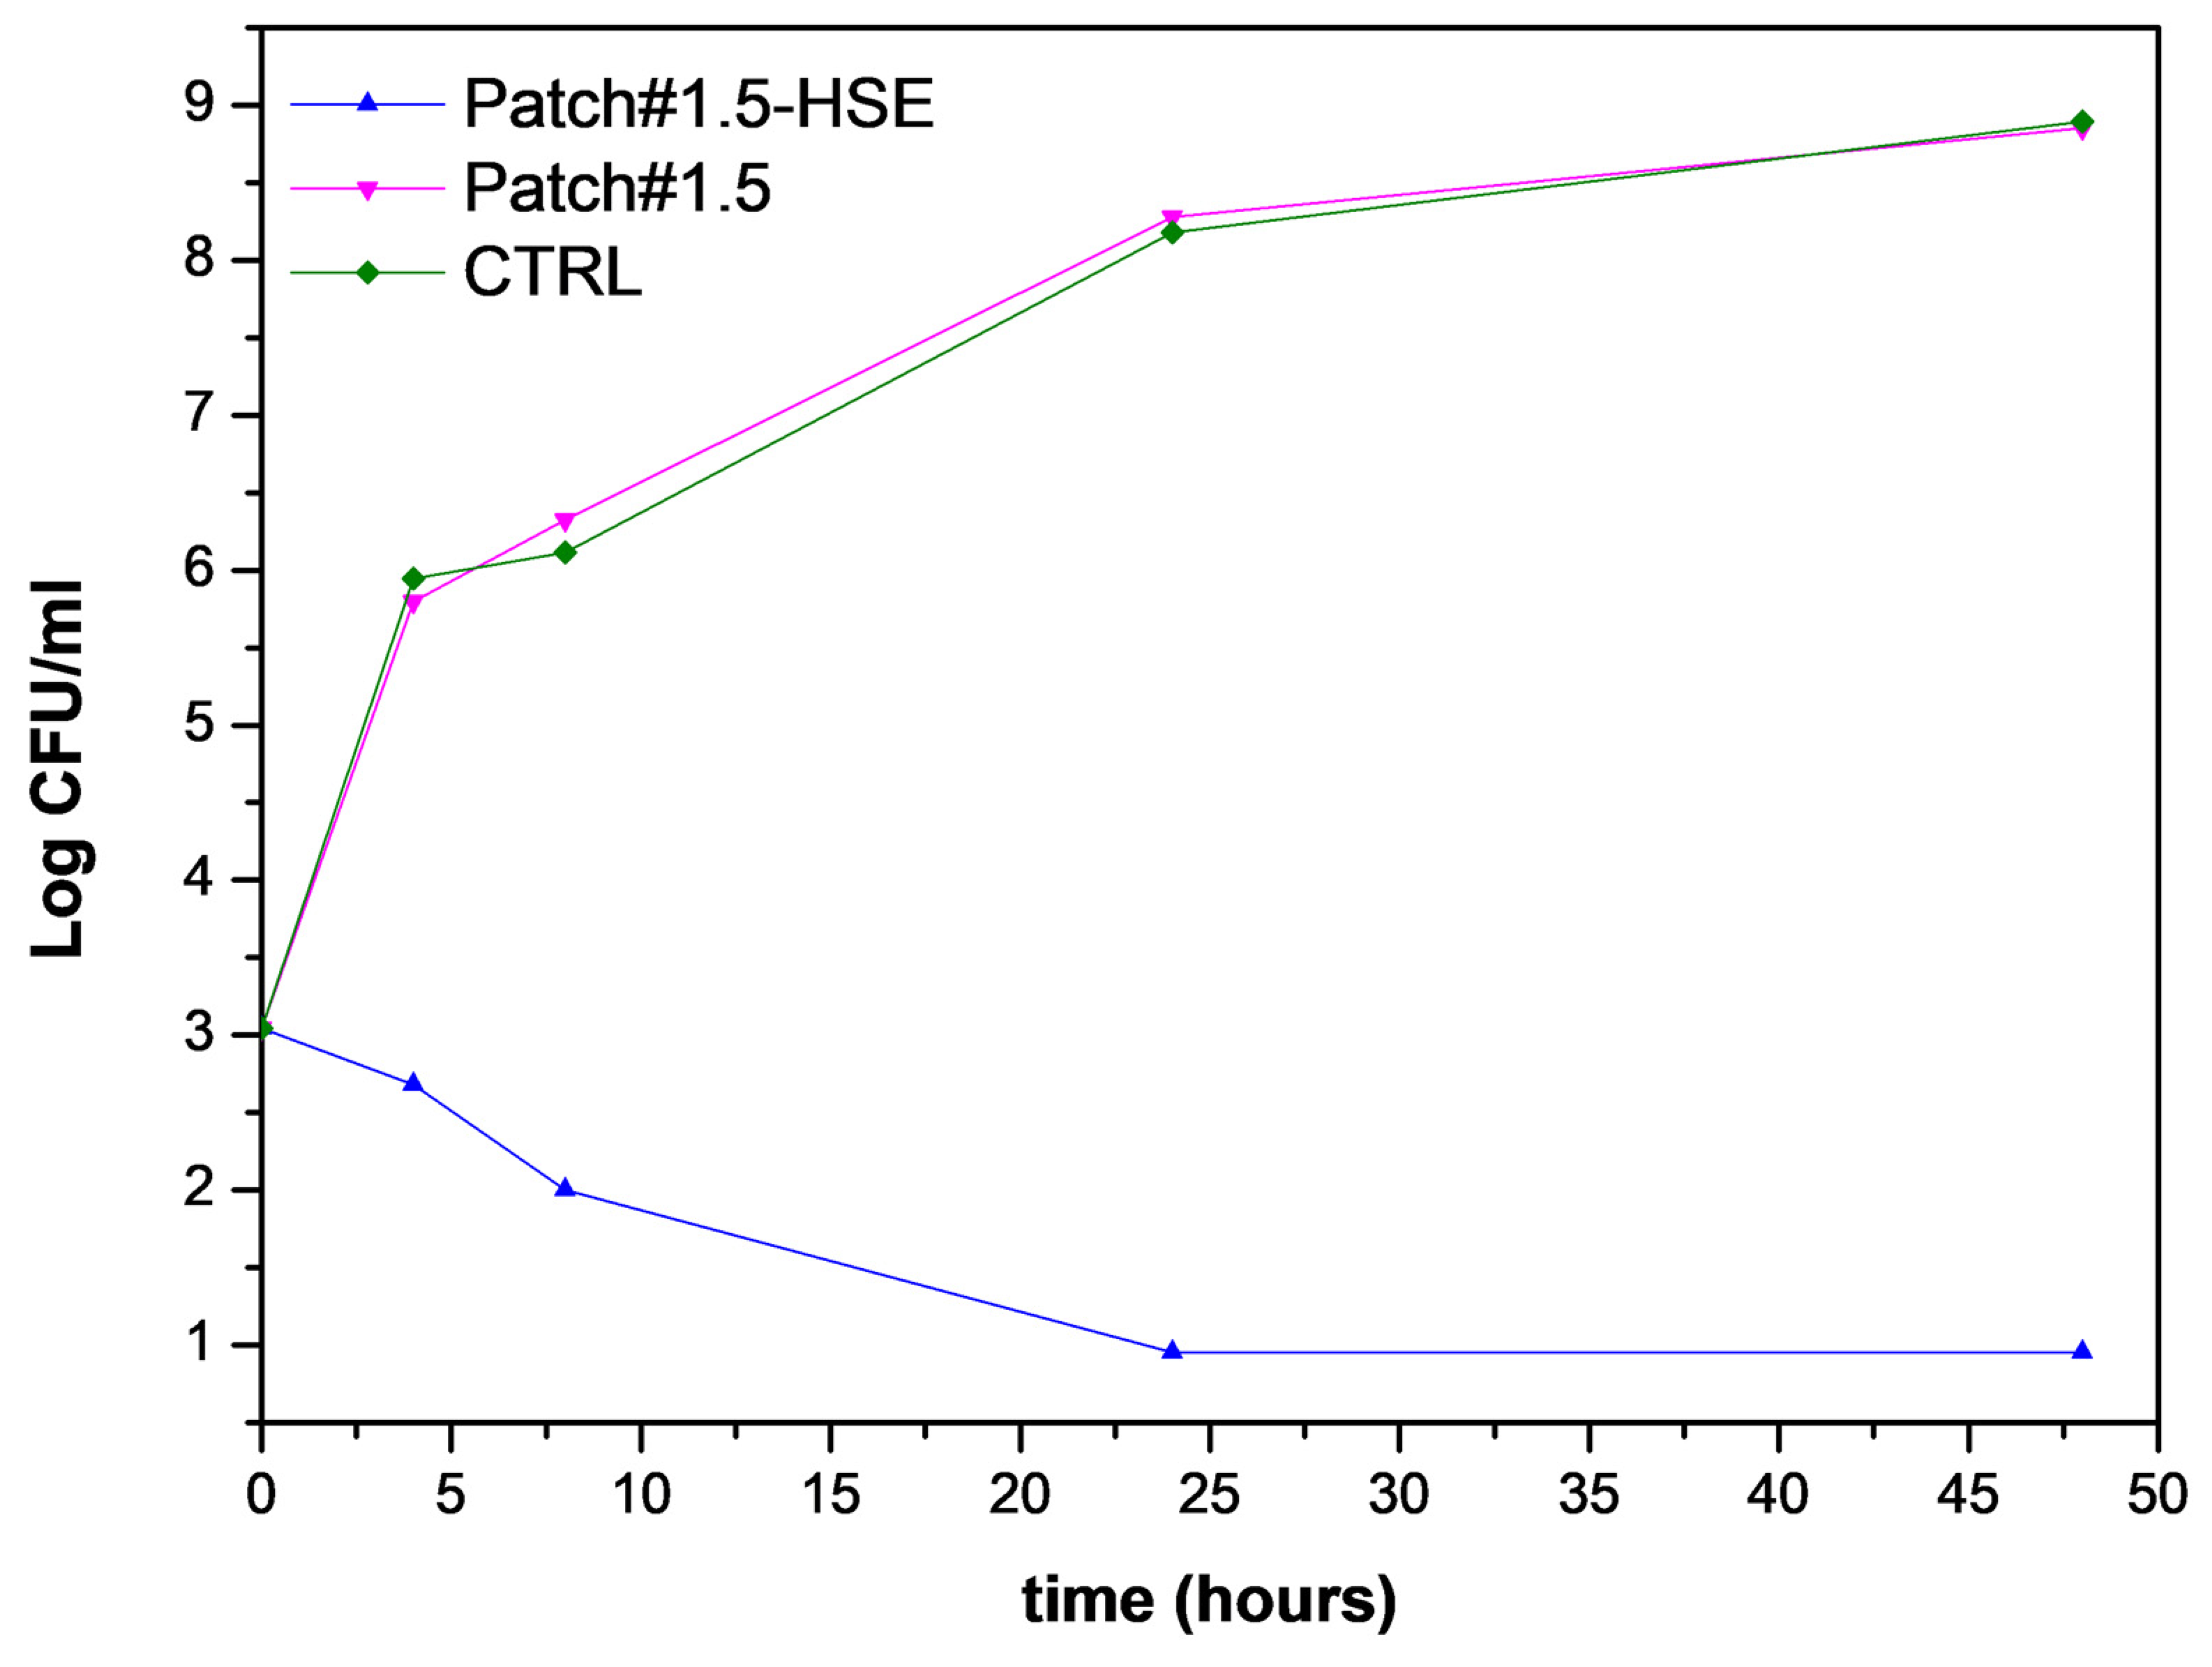

3.6.5. Antimicrobial Activity